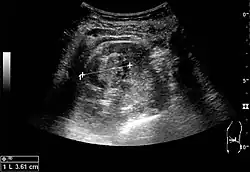

Renal cell carcinoma with both cystic and solid components located in the cortex. Measurement of tumor on the US image is illustrated by '+' and a dashed line.[3]

On renal ultrasonography, a solid renal mass appears in the US exam with internal echoes, without the well-defined, smooth walls seen in cysts, often with Doppler signal, and is frequently malignant or has a high malignant potential. The most common malignant renal parenchymal tumor is renal cell carcinoma (RCC), which accounts for 86% of the malignancies in the kidney. RCCs are typically isoechoic and peripherally located in the parenchyma, but can be both hypo- and hyper-echoic and are found centrally in medulla or sinus. The lesions can be multifocal and have cystic elements due to necrosis, calcifications and be multifocal (Figure 8 and Figure 9). RCC is associated with von Hippel–Lindau disease, and with tuberous sclerosis, and US has been recommended as a tool for assessment and follow-up of renal masses in these patients.[3]